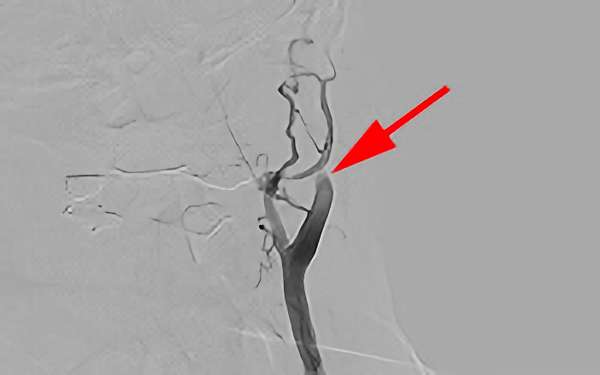

症例 '19年9月

No.

647

'19年9月23日

右中大脳動脈閉塞症

70代

院内外来

'19年9月